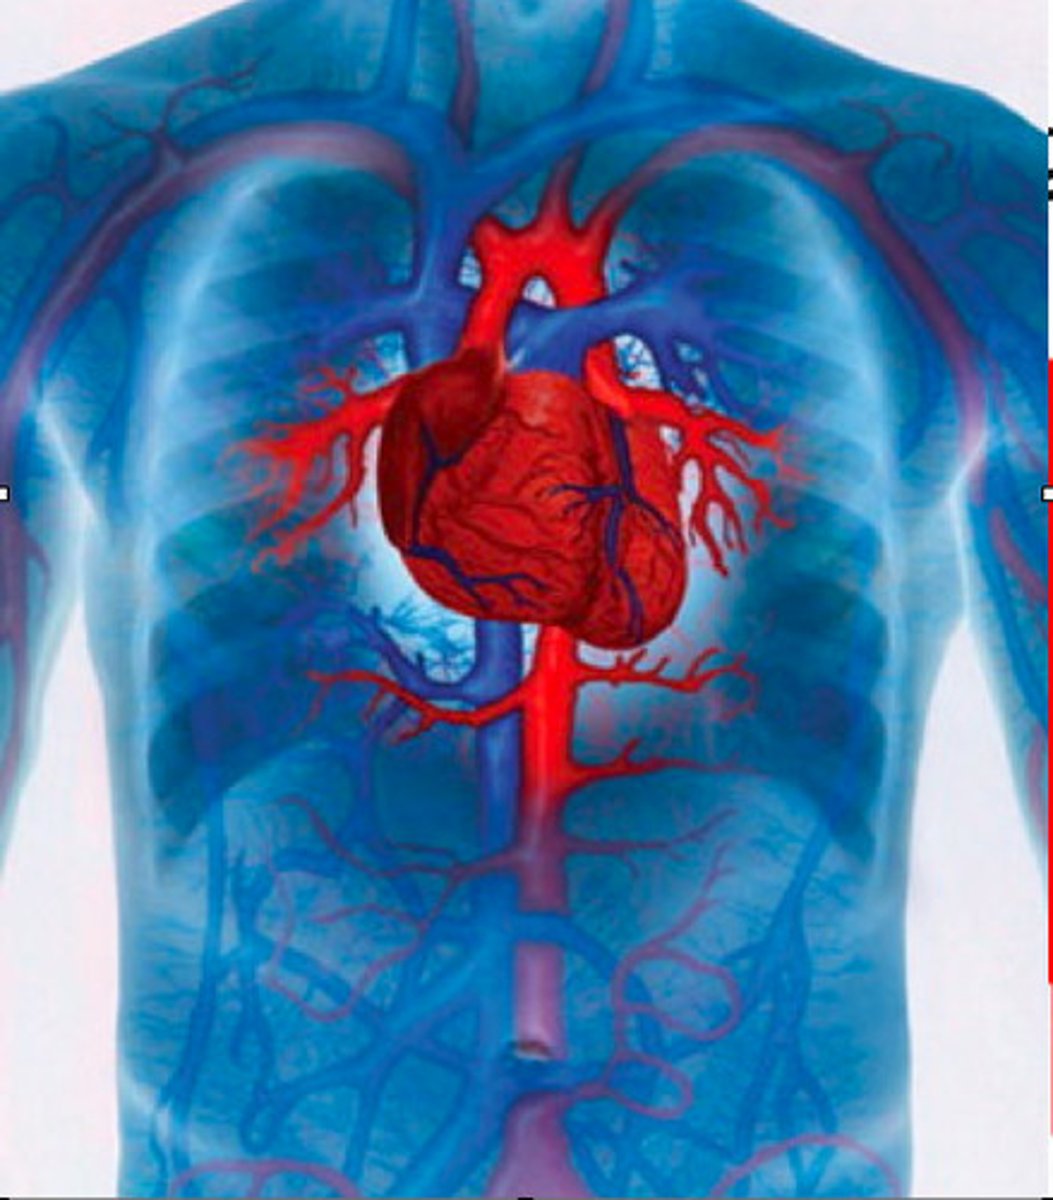

Cardiovascular physiology

It is the study of the heart and blood vessels.